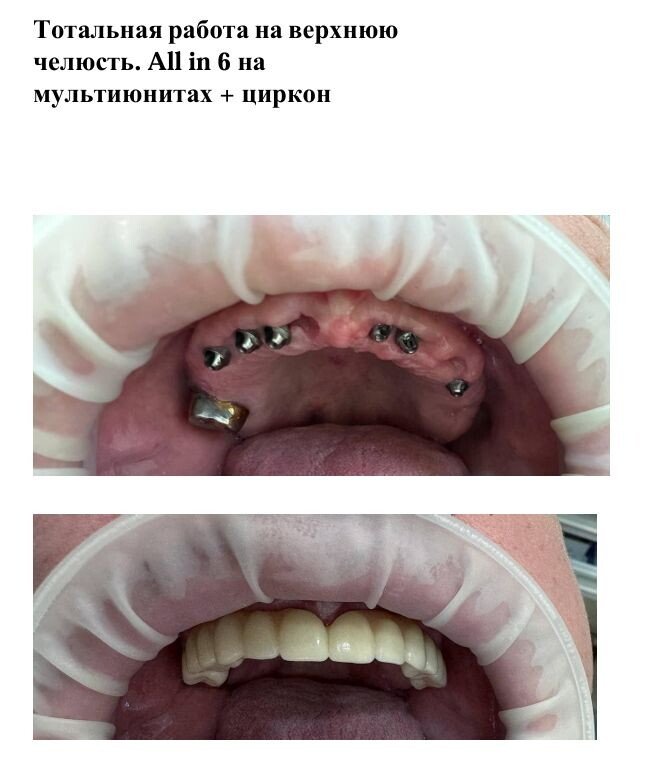

Фотогалерея